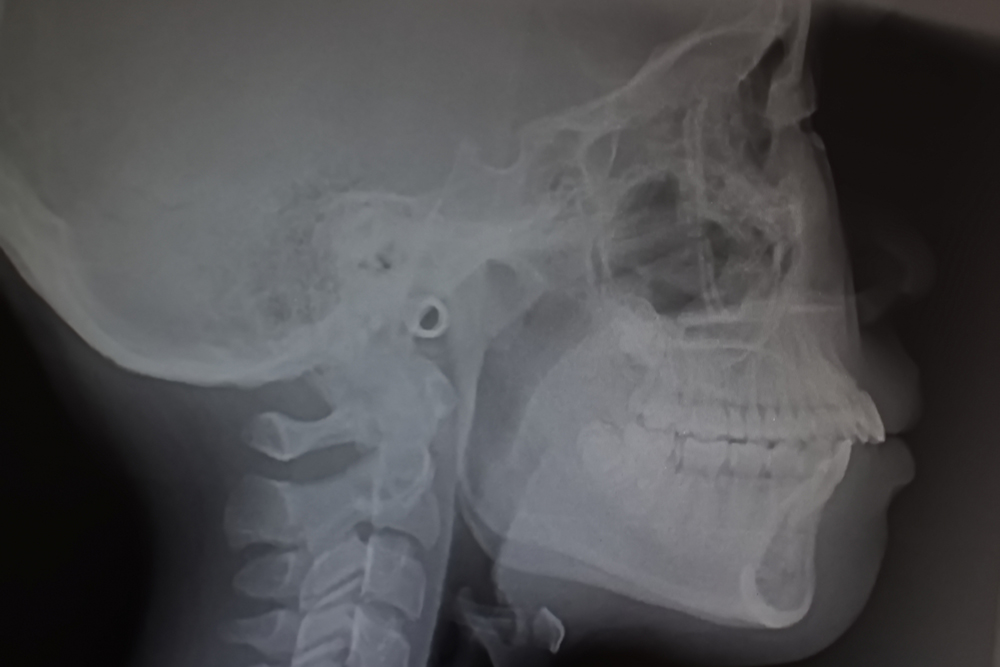

口ゴボは骨格・歯列・唇の位置関係が複合するため、正確な評価が重要です。当院ではセファログラム分析や顔貌写真を用い、上顎・下顎の前後位置、口元の突出量、Eラインとのバランスを詳細に確認します。

口ゴボの治療では、まずセファログラムや顔貌写真で骨格と歯列の位置関係を分析します。その結果に基づき、抜歯の必要性や適した矯正方法を判断します。